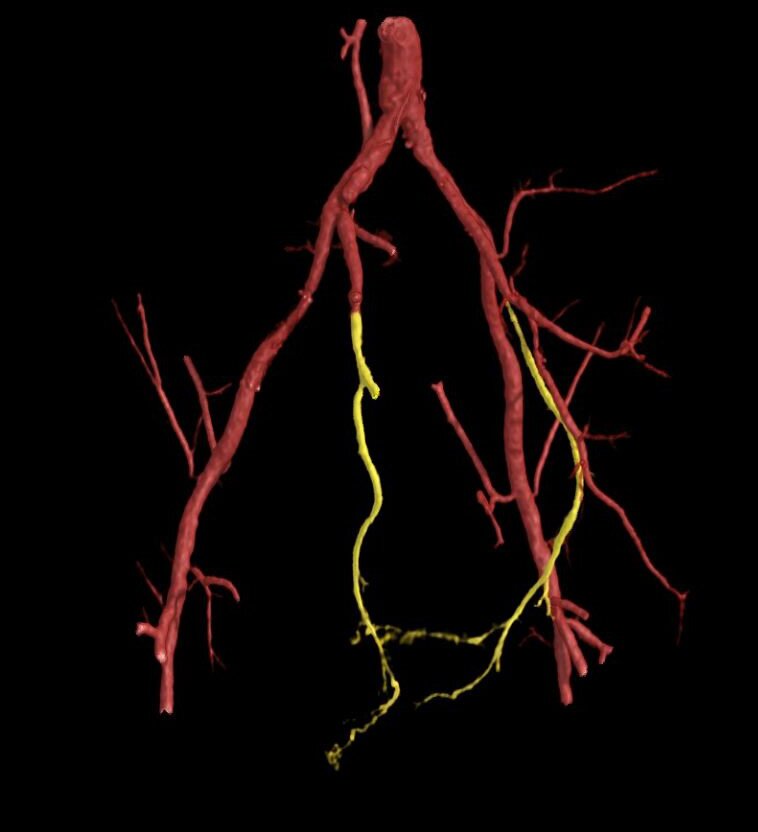

Dreidimensionale Rekonstruktion der Blutgefässe im Becken und im Penis vor der Planung einer allfälligen Therapie.